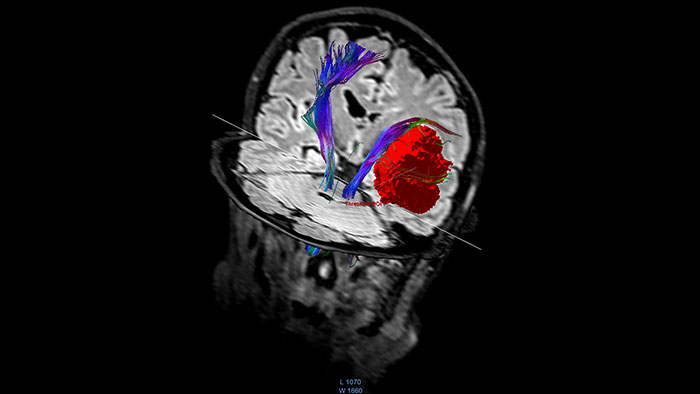

Visualize white matter connectivity in the brain

Provides visualization and quantification of white matter structure in the brain and spinal tracts using task guidance for generating common or user-defined tracts.

Analyze diffusion and anisotropic properties of tissue

Designed to analyze diffusion and anisotropic properties of tissue. The application evaluates DWI series to generate parametric maps such as ADC and eADC. For Diffusion Tensor Imaging data, additional parametric maps are generated, including fractional anisotropy, axial diffusivity or radial diffusivity.